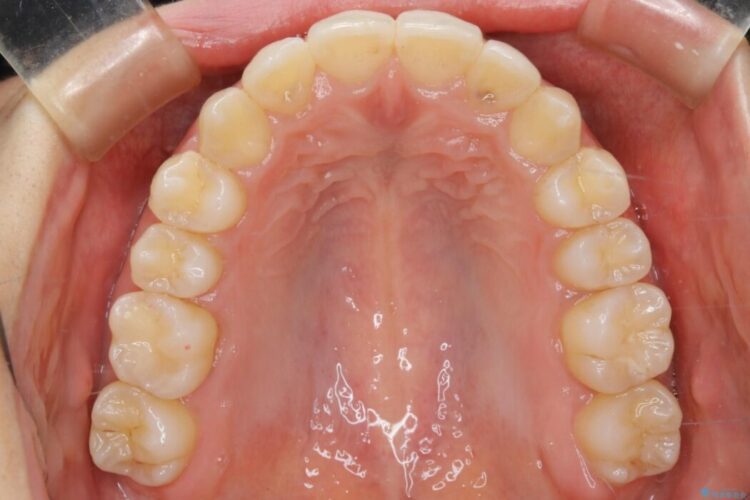

治療後写真を見ても歪みが解消され、歯列弓がきれいに整ったのが分かると思います。インビザラインをしっかりと装着されていたこともあり、矯正としては短期間の治療となりました。